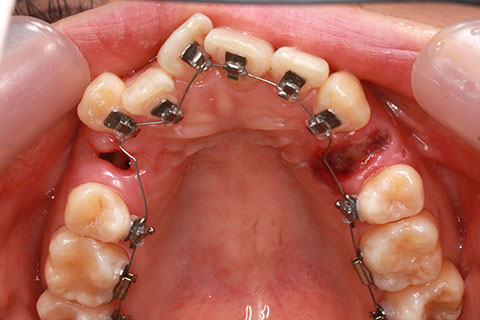

ハーフリンガル矯正3:上の歯のみ舌側矯正で治療(矯正期間24ヶ月)

治療前

治療中(開始直後)

治療中(開始半年後)

治療後

- 年齢・性別

- 25歳女性

- 治療期間

- 2年0ヶ月

- 抜歯

- 上下4番抜歯

- 治療費

- 110万円

- 治療内容

- 施術の副作用(リスク)

- 表側矯正と比較して、力学的な操作性が複雑なため、ボーイングエフェクトを起こしやすい。